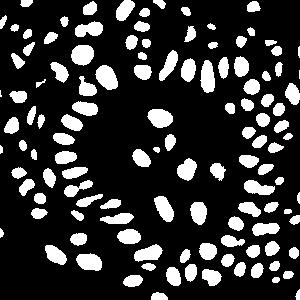

(a) image

(b) round 1

(c) round 2

(d) round 3

An example is shown in Fig. 2 to illustrate the masks in different rounds of self-training. The foreground nuclei annotation (green pixels) is kept unchanged during the iterations while the background area (pixels in black) grows up gradually. In the third round, the background has high accuracy and the ignored pixels (orange) are almost all nuclei.